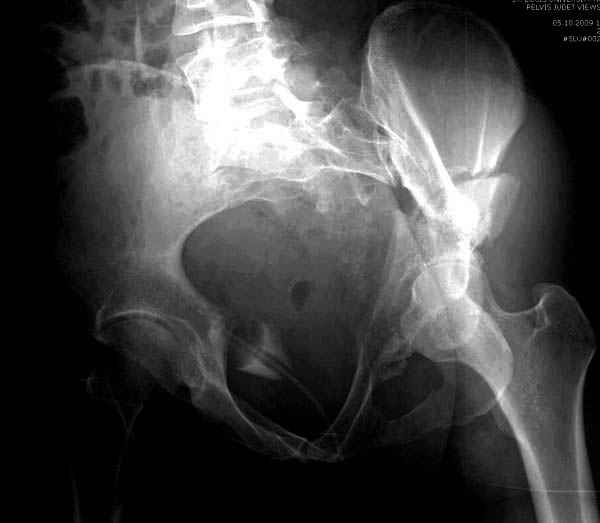

высылаю дополнительно сканы.

Судя по представленным реконструкциям (не очень хорошего качества - много наводок)

По отдельным срезам и тем более по реконструкции трудно судить о сращении крыла и задней колонны с осевым скелетом.

В большинстве случаев при двухколонных переломах

в итоге получается прочный бублик с дыркой. При эндопротезировании в дырку помещается головка, а чашка должна неплохо заклиниться в бублике.

Главное, чтобы бублик не был разорван, что не очень понятно на представленных снимках.

Поэтому хотелось бы дообследовать больного (разумеется включив стандартные проеции judet,и срезы показывающие сращение)

И наконец главное- какие жалобы у пациента, он нагружает ногу или нет, какая клиника, что-то все рентгенограмму бросились лечить?

Хорошо бы на рентгенограммы взглянуть и побольше срезов по своду. С каким отломком головка контактирует и как ее состояние.